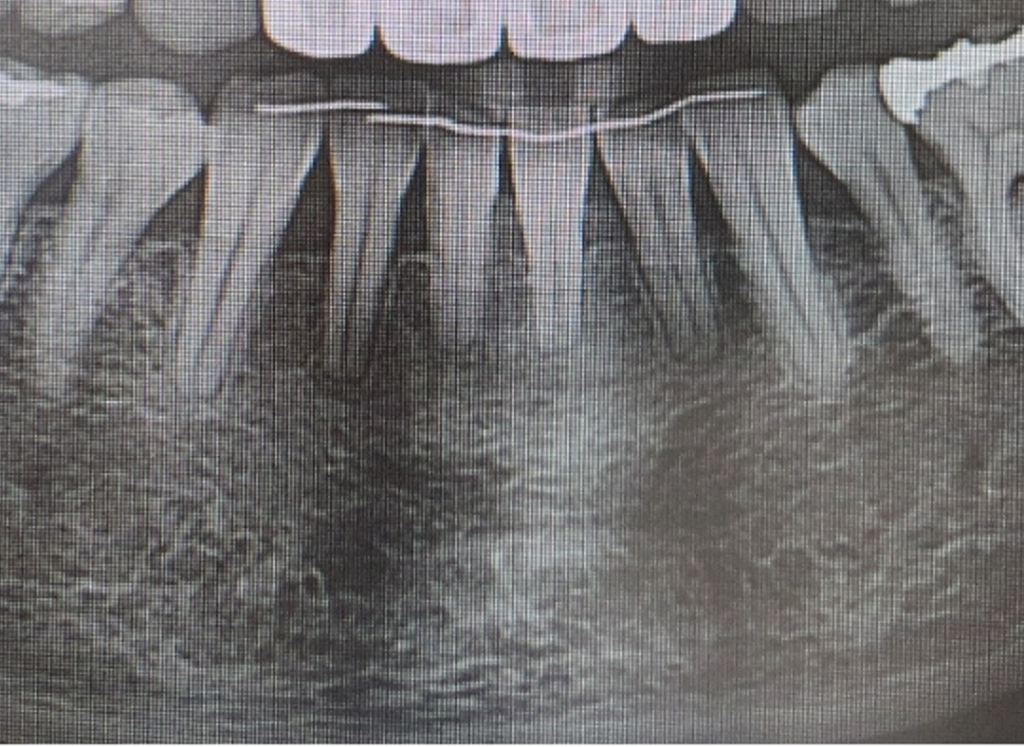

치아 뿌리도 너무 짧구요

블랙트라이앵글도 심합니다

잇몸도 내려갔습니다.ㅠ